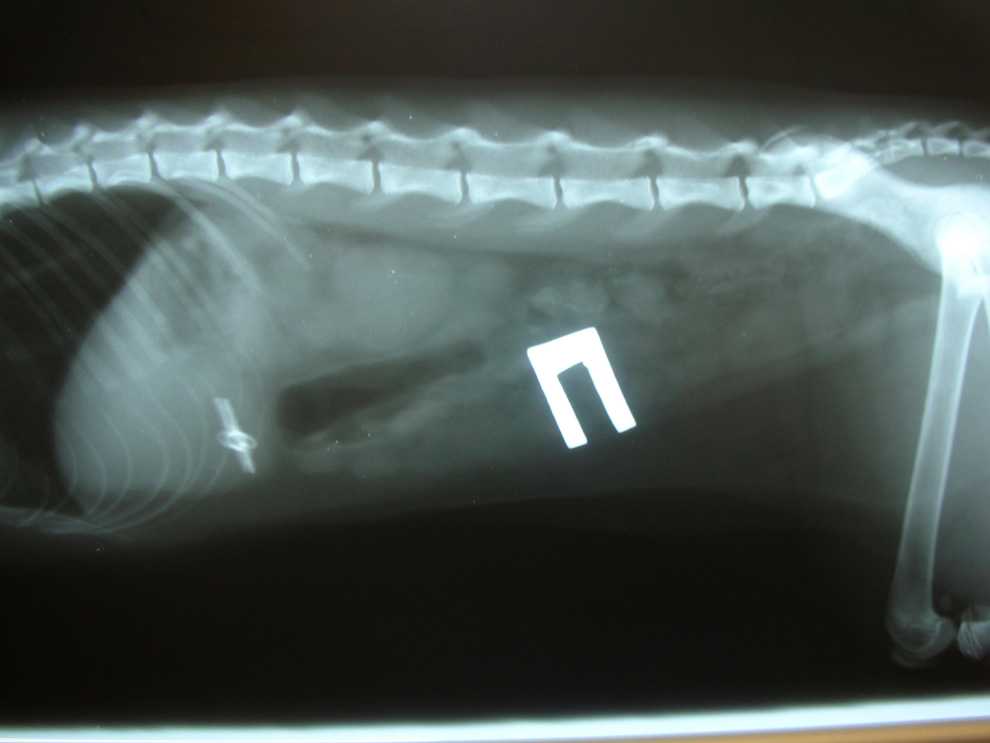

- Рентгенография поможет выявить наличие металлических, резиновых предметов, камней. На рентгене также видна деформация и другие изменения в органах пищеварительного тракта, характерные для присутствия инородного тела.

- Чтобы точно определить место предмета и проследить его продвижение по пищеварительному тракту, делается рентген с контрастным веществом. Чаще используется барий.